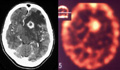

Different uptake patterns of radiopharmeceuticals as detected by SPECT may help differentiate pathologies. For example, Tl-201 can accurately distinguish primary cerebral lymphoma from infection processes, particularly cerebral toxoplasma encephalitis (31)(32)(33)(34). Uptake is due to an active cell membrane pump in the active, growing neoplastic tissue. Active lymphoma is considered when the intracranial Tl-201 SPECT activity is greater than the activity of the contralateral scalp (Figure 12). Non-lymphoma lesions do not display increased activity.

Figure 12

Figure 12 (Enlarge): Thallium SPECT imaging of primary CNS lymphoma. In this patient with AIDS, the contrast enhanced CT scan (left image) reveals a ring enhancing lesion with extensive surrounding edema. The appearance is consistent with toxoplasma abscess or CNS lymphoma. The thallium SPECT scan (right image) demonstrates intense uptake of radiotracer by the lesion, indicating that lymphoma. This diagnosis was subsequently confirmed by biopsy. (Images courtesy of A. Ruiz and J. Donovan-Post, U. Miami).